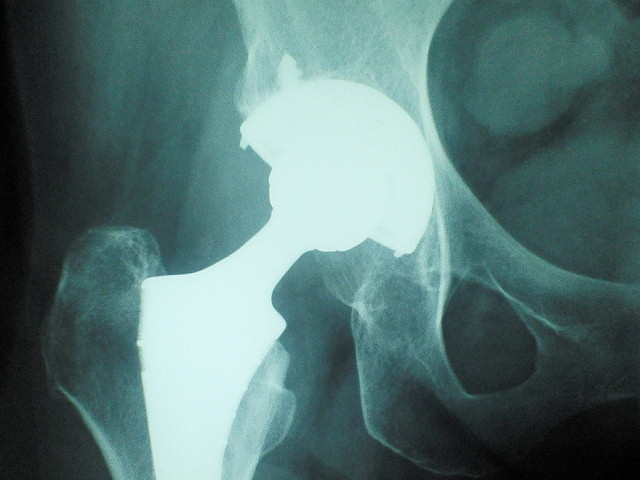

股関節の手術。。

右を手術したのは4年前だった。。